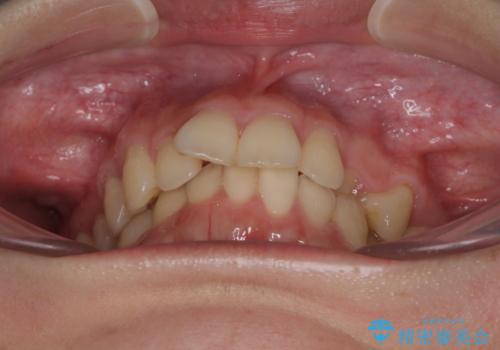

【モニター】犬歯のクロスバイトを目立たないワイヤー装置で

- 20代女性

- 矯正装置

- クリアブラケット

- 咬み合わせが悪いとのことで来院された患者様です。

ぱっと見はインビザラインによる矯正治療も可能と思われましたが、歯根が最も長い犬歯がクロスバイトになっており、インビザラインでは対応困難と判断され、ワイヤー装置にて矯正治療を行うこととしました。